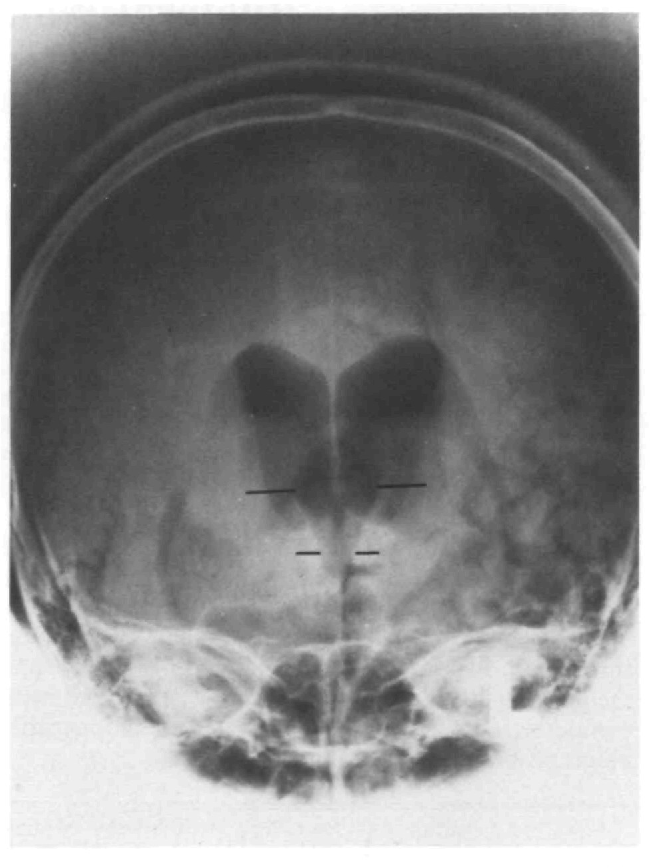

Uno de los rasgos distintivos del síndrome de Nothnagel es la parálisis ipsolateral del nervio motor ocular común. Esto significa que la lesión en el pedúnculo cerebeloso superior afecta el nervio motor ocular común del mismo lado del cerebro en el que se encuentra la lesión. El nervio motor ocular común es responsable del movimiento de ciertos músculos oculares que controlan la dirección de la mirada y los movimientos oculares.

Además de la parálisis ipsolateral del nervio motor ocular común, este síndrome también se caracteriza por la presencia de ataxia cerebelosa contralateral. La ataxia es un término que se usa para describir la falta de coordinación muscular, especialmente en los movimientos voluntarios. En este caso, la ataxia es «contralateral», lo que significa que afecta al lado opuesto del cuerpo con respecto a la lesión en el pedúnculo cerebeloso superior. Esto se debe a que el cerebelo, que desempeña un papel crucial en la coordinación motora, se encuentra en el lado opuesto del cerebro.